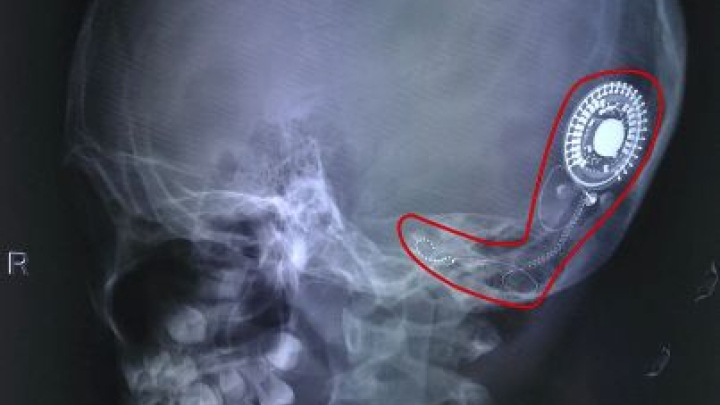

Lần đầu tiên nghe được tiếng nói nhờ cấy điện ốc tai, cô bé ở Đồng Nai mất vài giây ngơ ngác lặng người rồi...